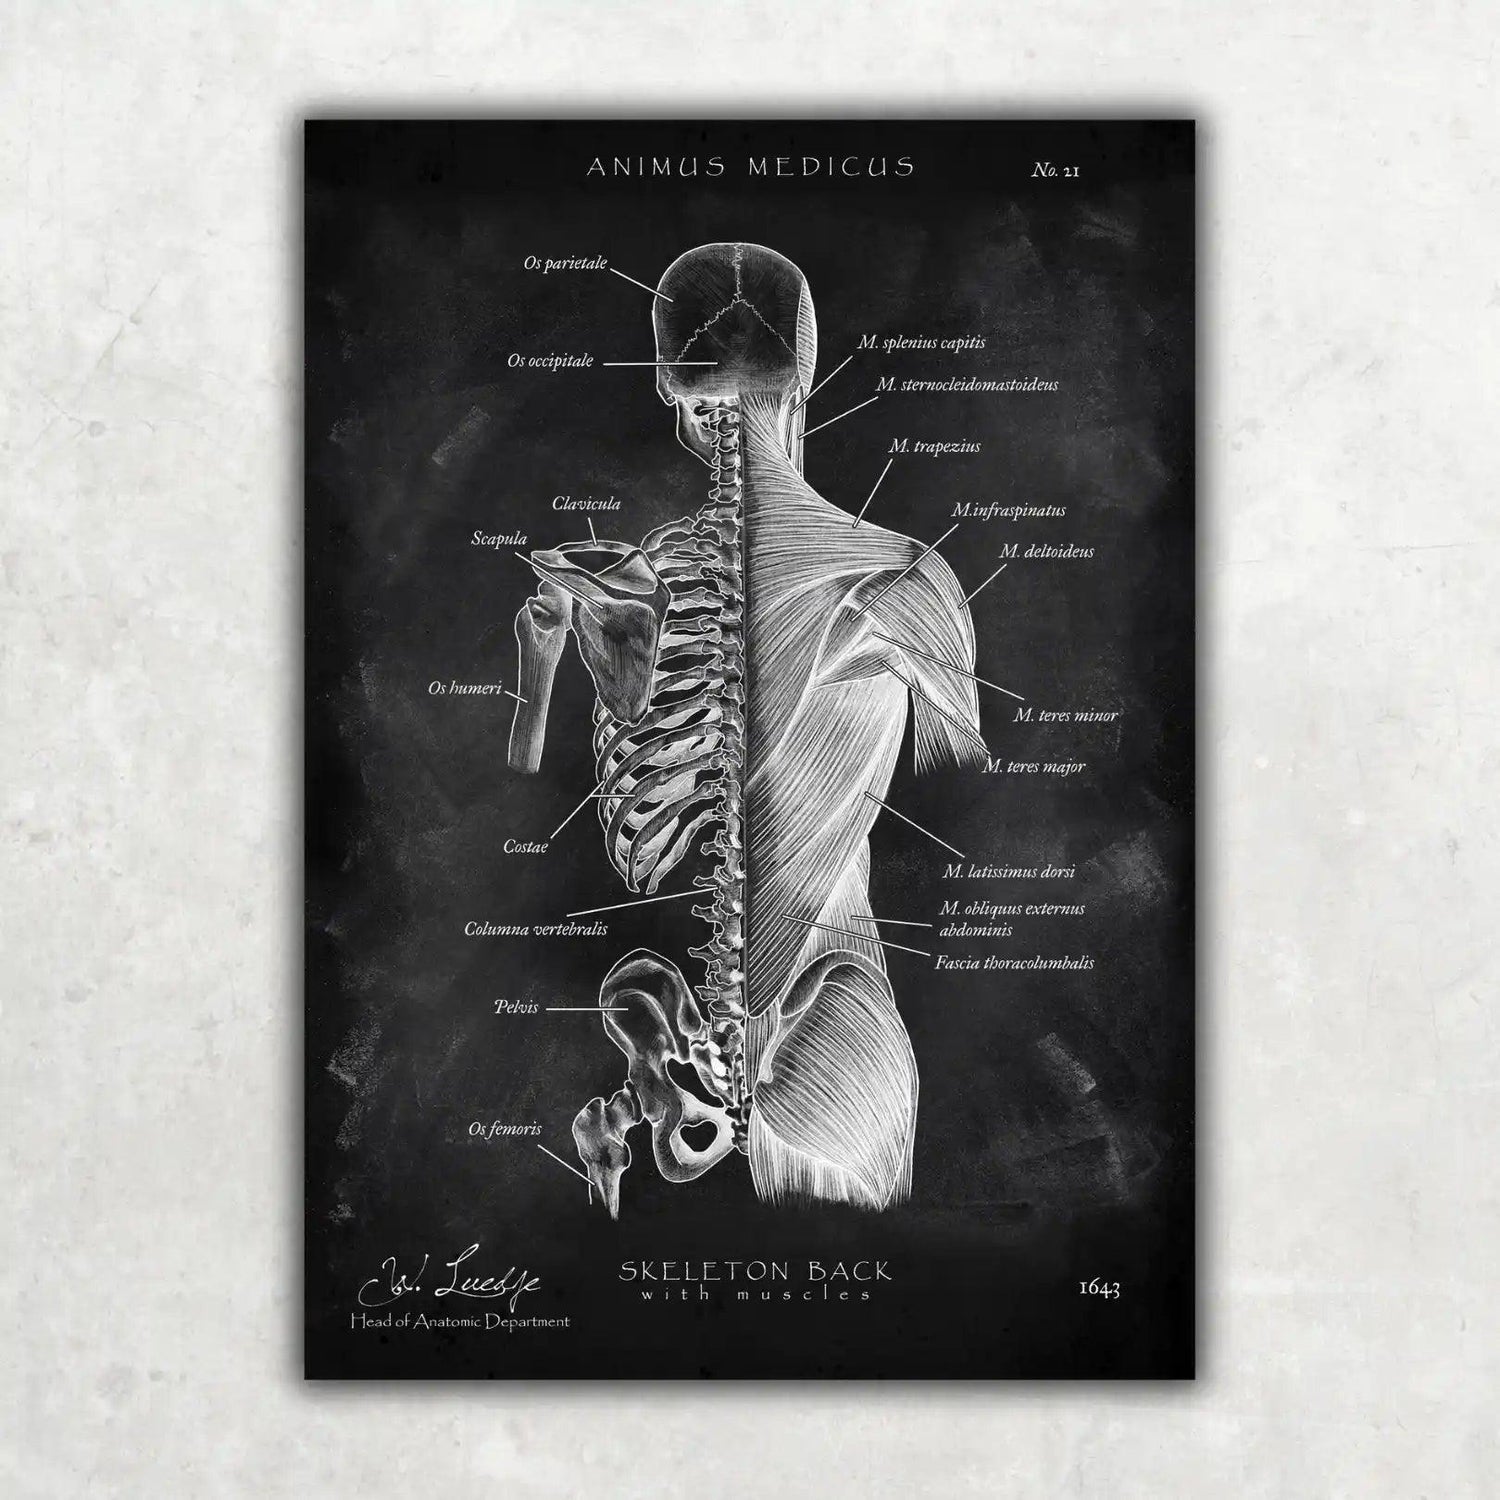

Warst du auf der Suche nach einer Möglichkeit, die faszinierende Anatomie des Herz-Kreislauf-Systems nicht nur zu lernen, sondern auch visuell zu erleben? Bei Animus Medicus findest du ästhetische Anatomie-Poster im Vintage-Stil, die medizinisches Wissen und kunstvolles Design perfekt vereinen. Entdecke jetzt unsere Kollektionen auf https://animus-medicus.de und bringe die Schönheit der Anatomie an deine Wände.